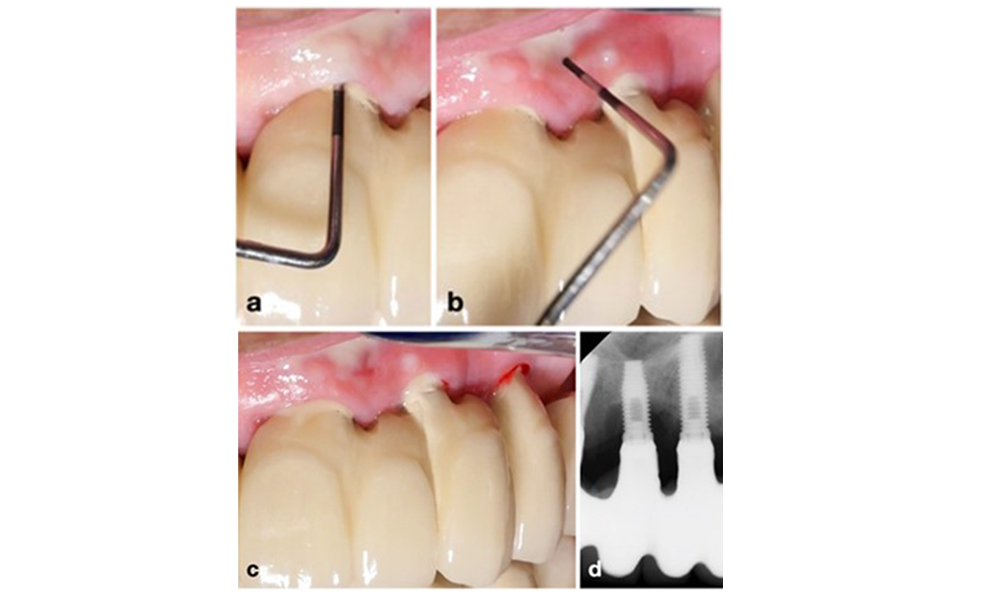

Le World Workshop on the Classification of Periodontal and Peri-Implant Diseases and Conditions de 2017 a établi des critères de diagnostic pour la mucosite péri-implantaire et la péri-implantite (Renvert et al. 2018). La mucosite péri-implantaire est définie comme (1) la présence d'une inflammation autour de l'implant (c'est-à-dire une rougeur, un gonflement, une ligne ou une goutte de saignement dans les 30 secondes suivant le sondage), associée à (2) l'absence de perte osseuse supplémentaire après la cicatrisation initiale (figure 1).

Implant en position 26 avec mucosite péri-implantaire (a-c). La valeur de la profondeur de sondage de 5 mm (b) reste cohérente avec la mesure prise quelques semaines après la mise en place de la reconstruction prothétique. Il y a un saignement au sondage (c) mais la radiographie n'indique pas de perte osseuse supplémentaire au-delà de ce qui est attendu pour un remodelage de l'os marginal (d).

Figure 1. Implant en position 26 avec mucosite péri-implantaire (a-c). La valeur de la profondeur de sondage de 5 mm (b) reste cohérente avec la mesure prise quelques semaines après la mise en place de la reconstruction prothétique. Il y a un saignement au sondage (c) mais la radiographie n'indique pas de perte osseuse supplémentaire au-delà de ce qui est attendu pour un remodelage de l'os marginal (d).